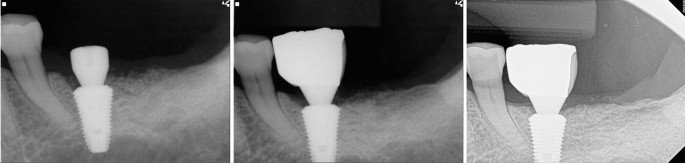

The ISQ of 14 out of the 32 implants was recorded (Table 1). Some records could not be completed because (1) surgery had been performed before the acquisition of the device, or (2) one of two stability ISQs was missing. The measured mean primary stability (ISQ) was 64.1 (±12.4). The mean secondary stability (ISQ) was 73.9 (±7.6), indicating a statistically significant increase in ISQ during the healing period (paired t-test; P=0.007).

The periapical views of groups I, II and III are shown in Figs. 2, 3, 4. Of the 32 teeth, ten were in group I, ten in group II, and 12 in group III (Table 3). In group I, two out of five new endodontically treated teeth were extracted with symptoms. Consequently, five of 10 teeth in group I had events. The remaining five teeth consisted of two endodontically treated teeth prior to implant surgery and three vital teeth with non-specific findings. Fig. 2 shows the healing aspect of one of three vital teeth in group I and a replaced implant with a new one due to failure in osseointegration, which was the only case of implant failure in the study. In group II, one of the vital teeth had symptoms and underwent RCT. In group III, a new RCT was performed on one vital tooth, which was subsequently extracted. There were no implant failures in groups II and III. Events among the three groups showed significant differences (Chi-square test, p=0.008).

New RCT (seven teeth) and subsequent extraction (three of the seven new RCT teeth) were performed for 32 injured teeth (21.9%). With three teeth being extracted, the remaining 29 teeth functioned well, showing a survival rate of 90.6% for the injured natural teeth. Of the 32 implants, one failed and was replaced with a new implant. The survival rate of the implants was 96.9 %.

From the viewpoint of implant stability, possibility of osseointegration without removal may be questionable when the implant contacted or invaded the adjacent root. In previous studies with miniscrews, miniscrew-root contact may cause the loss of miniscrew stability, which may be a major risk factor for failure16,18,19,22. In a study of beagle dogs, six screws were in contact with the root and five of them were lost. Conversely, as long as no contact was present between the root and miniscrew and the success rate was 100%16. In a similar study, out of 30 miniscrews with root contact, 25 failed, but 18 without contact, 8 failed only19. In another study, the failure rate of the miniscrews that invaded the roots was 79.2%, regardless of force application. This could be due to insufficient bone-implant contact for mechanical retention, damage to the surrounding tissue from miniscrew slip during insertion, and physiologic movement of the root during mastication18. In the present study, the ISQ of the measured implants increased significantly and osseointegration was not disturbed. Implant osseointegration and normal function continued for a long period. Even in group I, in which a relatively high failure rate of the invaded teeth was observed, of the 10 implants, only one resulted in the loss of osseointegration, and the remaining showed a stable bone level without pathological signs. This was the opposite results of previous animal studies using miniscrews. Considering the physiologic movement of invaded teeth during healing, dental implants showed higher stability than miniscrews. Dental implants could be maintained without immediate removal even when they invade the adjacent root.